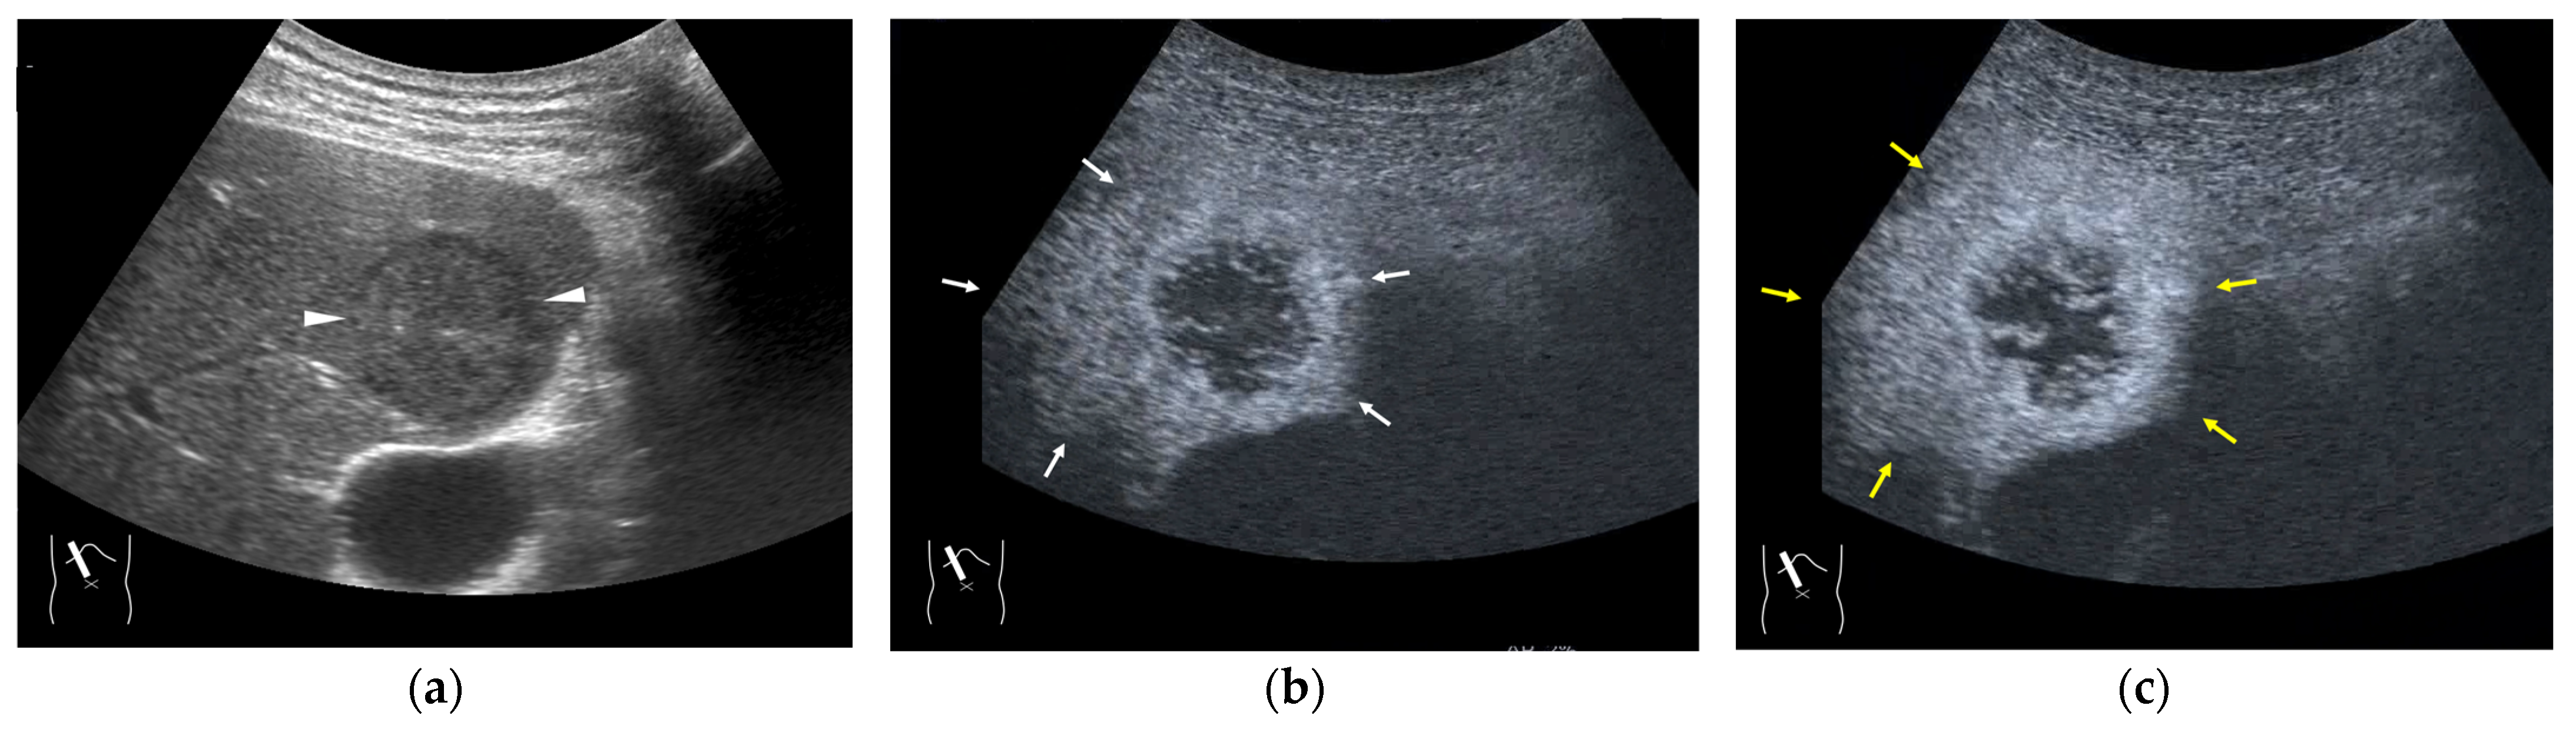

Figure 4.

Representative case of surgically resected well-differentiated HCC arising from minimally fibrotic (F1) liver: (a) B-mode reveals HCC in segment 6 (arrow heads). (b,c) Color Doppler shows tumor vascularities in a basket pattern (arrow heads) and a hepatic vein (arrows). (d) CEUS reveals a markedly enhanced HCC lesion (arrow heads). A hepatic vein (arrows) is enhanced immediately after tumor enhancement.